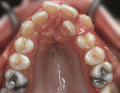

In addition to aesthetic reasons, some patients are referred to an orthodontist for functional reasons. Crooked, crowded teeth are difficult to clean and susceptible to decay or gum problems. Some kinds of imperfect bites can aggravate joint discomfort (TMD). Some adults require orthodontics as one of the stages in restorative dentistry (i.e., implants, crowns and bridges).